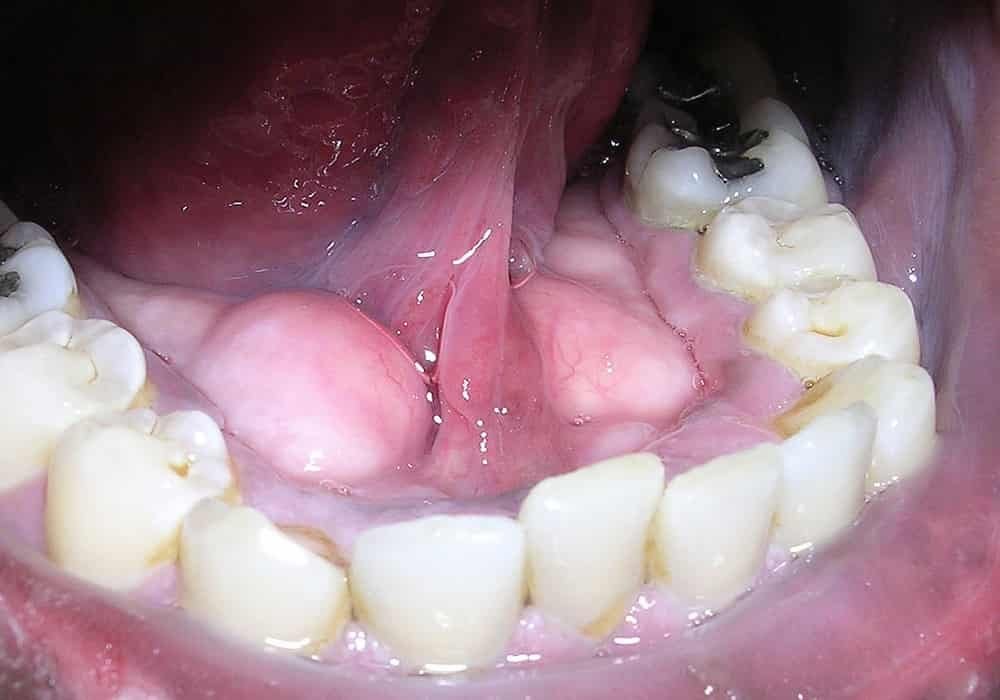

Ketika beberapa lapisan plak bergabung dengan mineral yang ada dalam air liur Anda, ia mengeras menjadi substansi kalsifikasi berkapur putih (atau agak gelap) yang disebut tartar.

Bahkan jika Anda merawat gigi Anda di rumah, Anda masih memiliki bakteri di mulut Anda. Mereka mencampur dengan protein dan produk sampingan makanan untuk membentuk film lengket yang disebut plak gigi. Lendir atau cairan ini melapisi gigi Anda, berada di bawah garis gusi Anda dan menempel pada tambalan atau pekerjaan gigi lainnya. Plak membawa bakteri yang dapat merusak enamel gigi dan menyebabkan gigi berlubang. Tetapi jika Anda membuang plak secara teratur, Anda dapat mencegah kerusakan gigi permanen dan penyakit gusi.

Masalah yang lebih besar muncul, namun, jika plak tetap di gigi Anda dan mengeras menjadi karang gigi. Menghilangkan karang gigi yang sudah terbentuk merupakan hal yang sangat susah. Anda harus ke dokter gigi untuk membersihkannya.

Tartar, juga disebut kalkulus, terbentuk di bawah dan di atas garis gusi. Ini kasar dan berpori dan dapat menyebabkan gusi surut dan penyakit gusi. Itu harus dihapus dengan alat khusus di tempat dokter gigi.